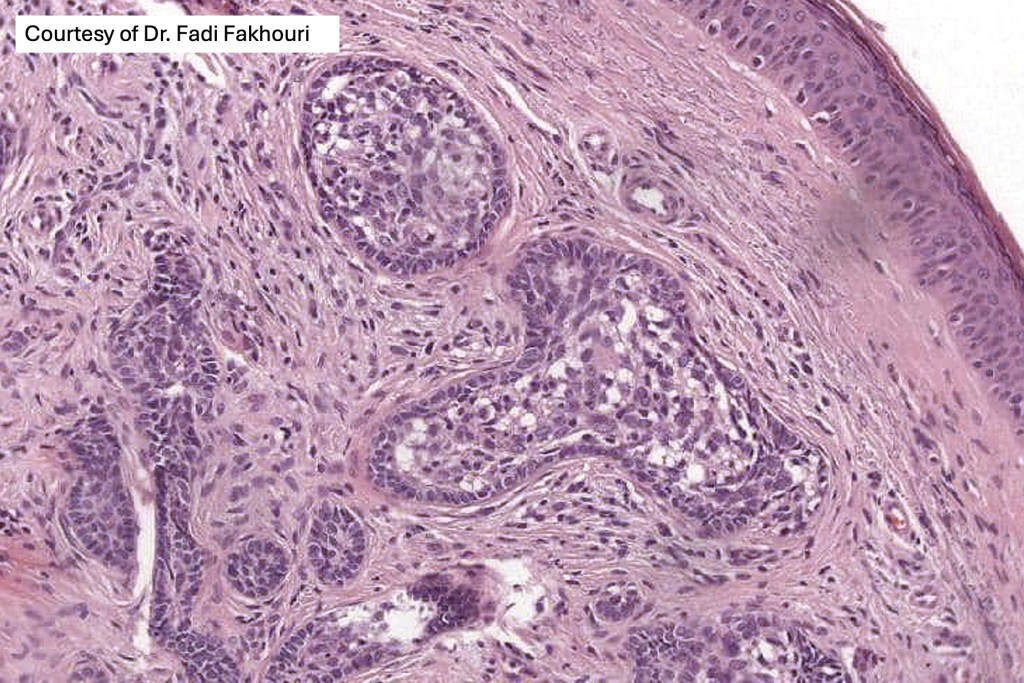

•Dermal nodule, rarely extends into subcutaneous fat

•Irregular lobules of epithelial cells embedded in a dense fibrous stroma

•Peripheral rim of darkly staining basaloid cells surrounding larger pale staining cells with vesicular nuclei with often prominent eosinophilic nucleoli

•Central cells PAS positive (glycogen)

•No retraction artifact or stromal mucin

•Admixed lymphocytes (an obligatory feature)

•Germinal centers sometimes present